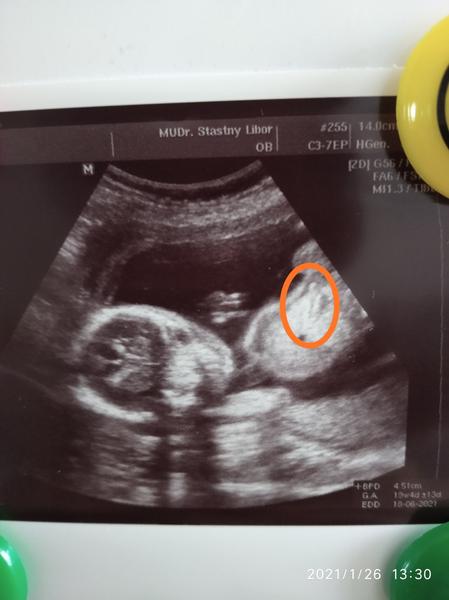

@lili1688 Pokud jste pozorovala utz, tak jste si jiste vsimla, ze se miminko ruzne hybe a doktor zameruje ruzne casti tela nebo je dokonce prosviti.

To, co mate zakrouzkovane muze byt cokoli co se vyskytuje okolo hrudniku nebo bricha. Miminko se zrovna hybalo a doktor udelal screen ve chvili, kdy se tam proste zobrazilo “tohle”.

Pohlavi to urcite neni a dal je asi jedno co to je, ne? 🤷🏼♀️